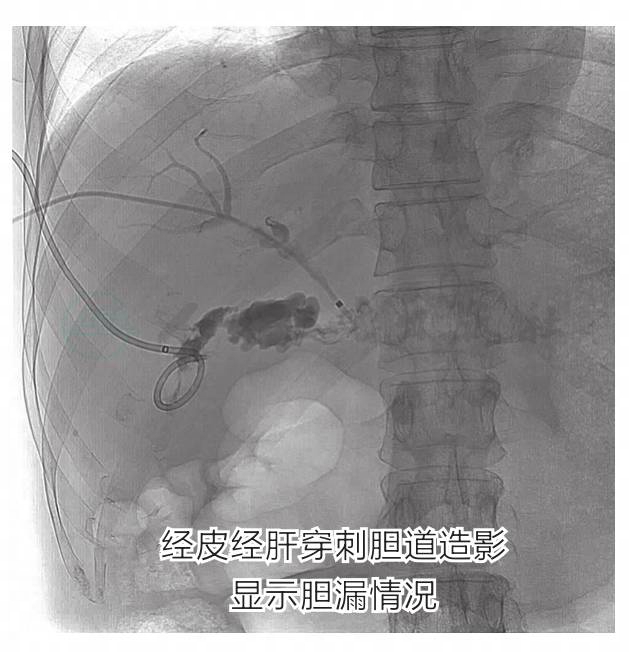

于肝移植术后第6天行ERCP造影未发现造影剂外漏(图8),在肝肾间隙形成血肿,约11cm×9cm,给予穿刺置管引流,每日引流出约20~30ml暗红色液体,血肿范围缩小为7.8cm×4cm(图9)。肝移植术后1个月起,无明显诱因出现发热伴寒战,体温最高39.3℃,白细胞及中性粒细胞比值均相应升高(图10)。血培养提示:阴沟肠杆菌亚种。腹腔穿刺置管每日可引流200ml黄绿色胆汁样液体,并行PTBD胆道外引流术(图11)。

回顾患者术中情况,由于三系细胞减少,所以选择切除脾脏,由于患者系二次腹部手术,且二次手术前行多次介入治疗,手术部位粘连严重,解剖困难,手术操作复杂。因此,术后脾窝引流管引流出大量暗红色血性液体,考虑手术后凝血机制紊乱合并创面出血。虽经保守治疗出血停止,但导致肝肾间隙残留大量凝血块组织,进而合并感染,导致胆道吻合口漏。肝移植术后胆漏的治疗除了抗感染等常规措施外,最重要的是以最快的速度找到胆漏原因并进行有效的引流。可选用的方法包括:①内镜检查:ERCP治疗适用于未进行胆肠吻合的患者,但有出血及诱发胰腺炎的风险;PTBD适用于肝内胆道增宽的患者;②外科手术:剖腹探查是最有效的胆道引流方法,但患者胆漏严重时通常腹腔粘连严重,解剖层次不清,手术难度大,易造成副损伤。因此,应先行通过微创外引流方式改善患者胆管炎症状,择期行胆肠Roux-en-Y吻合术。

4.处理过程

患者在积极抗感染的同时,先行ERCP术,向胆总管内注入造影剂后可见造影剂外漏征象,胆总管中段局限性管腔狭窄,多次尝试未能置入支架。再行PTBD胆道外引流及抗感染治疗。感染控制4个月后行胆肠吻合术。术后恢复良好,未再诉发热等胆管炎症状。